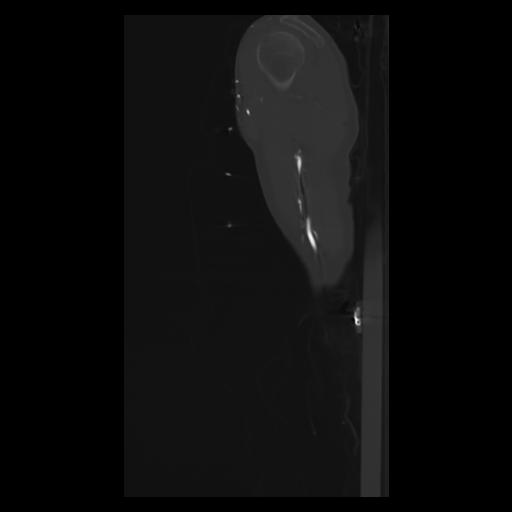

30 CUERPO,CE,Sagittal,3.000,CUERPO,Sagittal,